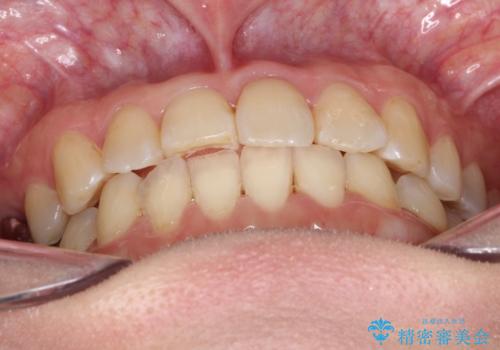

- 前歯の歯並びが気になるとのことで来院されました。

右上の1番目の歯が内側に入り込んでしまっており、その歯がの先端がすり減ってしまっていました。

インビザラインによる矯正治療で前歯の歯並びを改善し、セラミッククラウン装着により歯の形態の回復をする計画としました。

矯正とセラミックを併用することで、より完成度の高い状態に仕上げることができました。